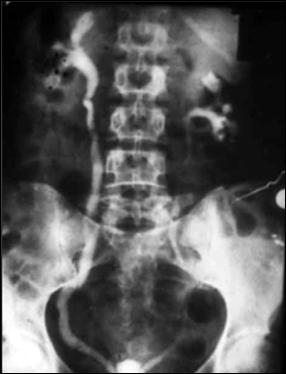

Diagnosticul diferential cu tuberculoza urogenitala

Vezica urinara are contururi greu delimitabile pe cistografie si pacientul are ureterohidronefroza bilaterala.

Figura 57. Vezica urinara mica |

Vezica urinara mica, scleroasa, cu rinichi drept unic chirurgical, uretero-hidronefroza gr I

Figura 59. Vezica urinara "crispata", cu ureterohidronefroza bilaterala. |